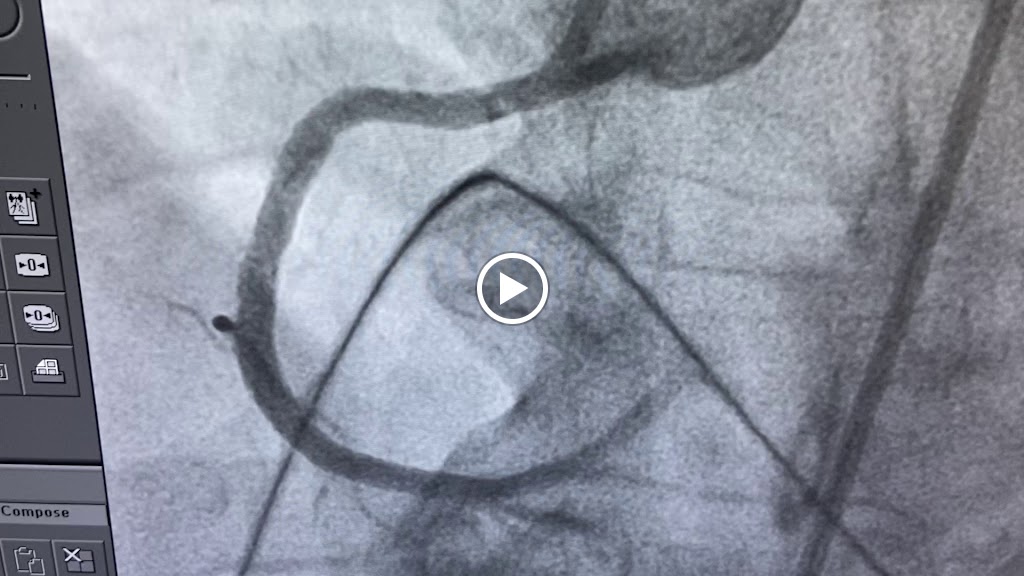

Heart Screening, High Blood Pressure, Stroke Screening, Peripheral Arterial Disease, Aneurysm Screening, Sudden Death Screening, Nuclear Stress Test, Best Cardiologist In Pune. I am passionate about treatment of heart attack using most modern technologies of primary angioplasty and delivering quality cardiac healthcare in India. If you want me to manage your dear one's case in Pune, please call me directly on my phone 7719972828 and I will manage the rest. thanks

I had my coronary angiography done by Dr Rahul sir.He has excellent skills,confidence and knowledge of his subject and he is very competent cardiologist. He trained at Cambridge and New York and this is evident in his skillset. Highly recommended

We underwent an angioplasty procedure, for my father and I cannot thank Dr. Rahul Sawant Sir enough for the exceptional care and professionalism throughout the entire process. From the initial consultation to the post-procedure follow-ups, Dr. Sawant Sir was incredibly thorough, compassionate, and reassuring. The procedure itself went smoothly, and we felt it was in the safest hands. Dr. Rahul Sawant Sir took the time to explain everything in detail, addressed all our concerns patiently, and ensured we are comfortable and well-informed at every step. Thanks to Dr. Sawant Sir and the wonderful team, I highly recommend Dr. Rahul Sawant to anyone in need of cardiac care -- truly one of the best in the field!